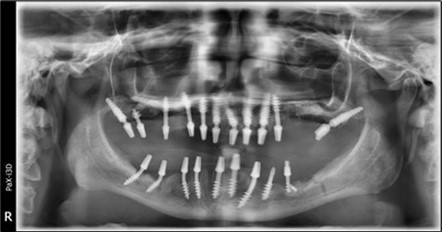

Plexus anesthesia is used in all working areas with Articaine 40 mg/0.01 mg/ml adrenaline. For mucosal disinfection, Betadine 10% is used.Two stage implants are removed either by simple extraction with forceps and an elevator or by using an osseous bur in cases where they cannot be easily removed using the first method. The remaining teeth are extracted, and the crest is regularized to avoid excessive future resorption, as well as to create an alveolar crest with a favourable resorption optical level for aesthetics (Figure 6, Figure 7).

In the upper anterior region, after extractions and regularization, marginal gingival connective tissue located palatine is harvested for use in augmenting the anterior area. This tissue is de-epithelized with a scalpel and kept in saline solution until used (Figure 4, Figure 5). The implants used are BCS corticobasal implants in areas with significant bone loss, and TPG compression implants, both from Dr. Ihde Dental AG, for post-extraction areas and regions with a large amount of trabecular bone but of poor quality (D3-D4). Both types of implants have a polished surface to reduce bacterial adhesion, and they feature a 2mm prosthetic collar that can be bent to parallelize the prosthetic part of the implant according to prosthetic requirements (Figure 3). The only exception to this parallelization through bending is the TPG implant in the maxillary-sphenoid fusion area (quadrant 2), were, due to lower torque, a prefabricated parallelization sleeve with a 25° angle was preferred. This sleeve was cemented before the impression was taken (Figure 3).

A total of 11 implants is placed in the maxilla, including compressive TPG implants with a polished surface in the maxillary-sphenoid fusion area (Figure 3, Figure 9). Similarly, in the anterior region, final fixation is achieved in the nasal cortex, and BCS corticobasal implants are added in areas with massive bone loss in the frontal region (Figure 3, Figure 8, Figure 11). Additionally, in the palatal sinus cortical area, with the aim of avoiding the addition and sinus lift zone where the second cortical bone no longer exists, 3 implants are placed, 2 in quadrant 1 and 1 in quadrant 2 (Figure 3, Figure 8). Through the Caldwell-Luc sinus lift procedure, the sinus cortical bone is displaced to allow the placement of the graft material and elevation of the sinus membrane. This sinus cortical is no longer recreated at the junction of the graft material and mucosa-sinus membrane, making it impossible to place a corticobasal implant, which relies on the second cortical bone. In the distal mandibular area, after the removal of two stage implants due to massive destruction in quadrant 3, implant placement distal to the mylohyoid line is not possible, as in quadrant 4 (Figure 10). A re-intervention occurs after 5 months to stabilize the area (Figure 12, Figure 14). Also, at the moment of fixation, the tip of one implant fractures, and the decision is made to leave it in place due to regional bone destruction, in order to avoid enlarging the bone defect.

In the interforaminal area (Figure 3, Figure 13), 6 corticobasal implants are also placed. The increased number of implants is due to the poorly represented distal area that needs to be compensated.

Figure 3.Panoramic pictures after removal of implants affected by peri-implantitis, extractions, alveolar crest regularization, and insertion of corticobasal and TPG implants (07.2022)